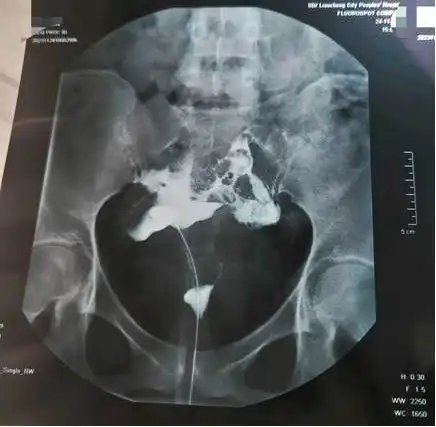

这样的输卵管是不是不通呢各位帮忙看下